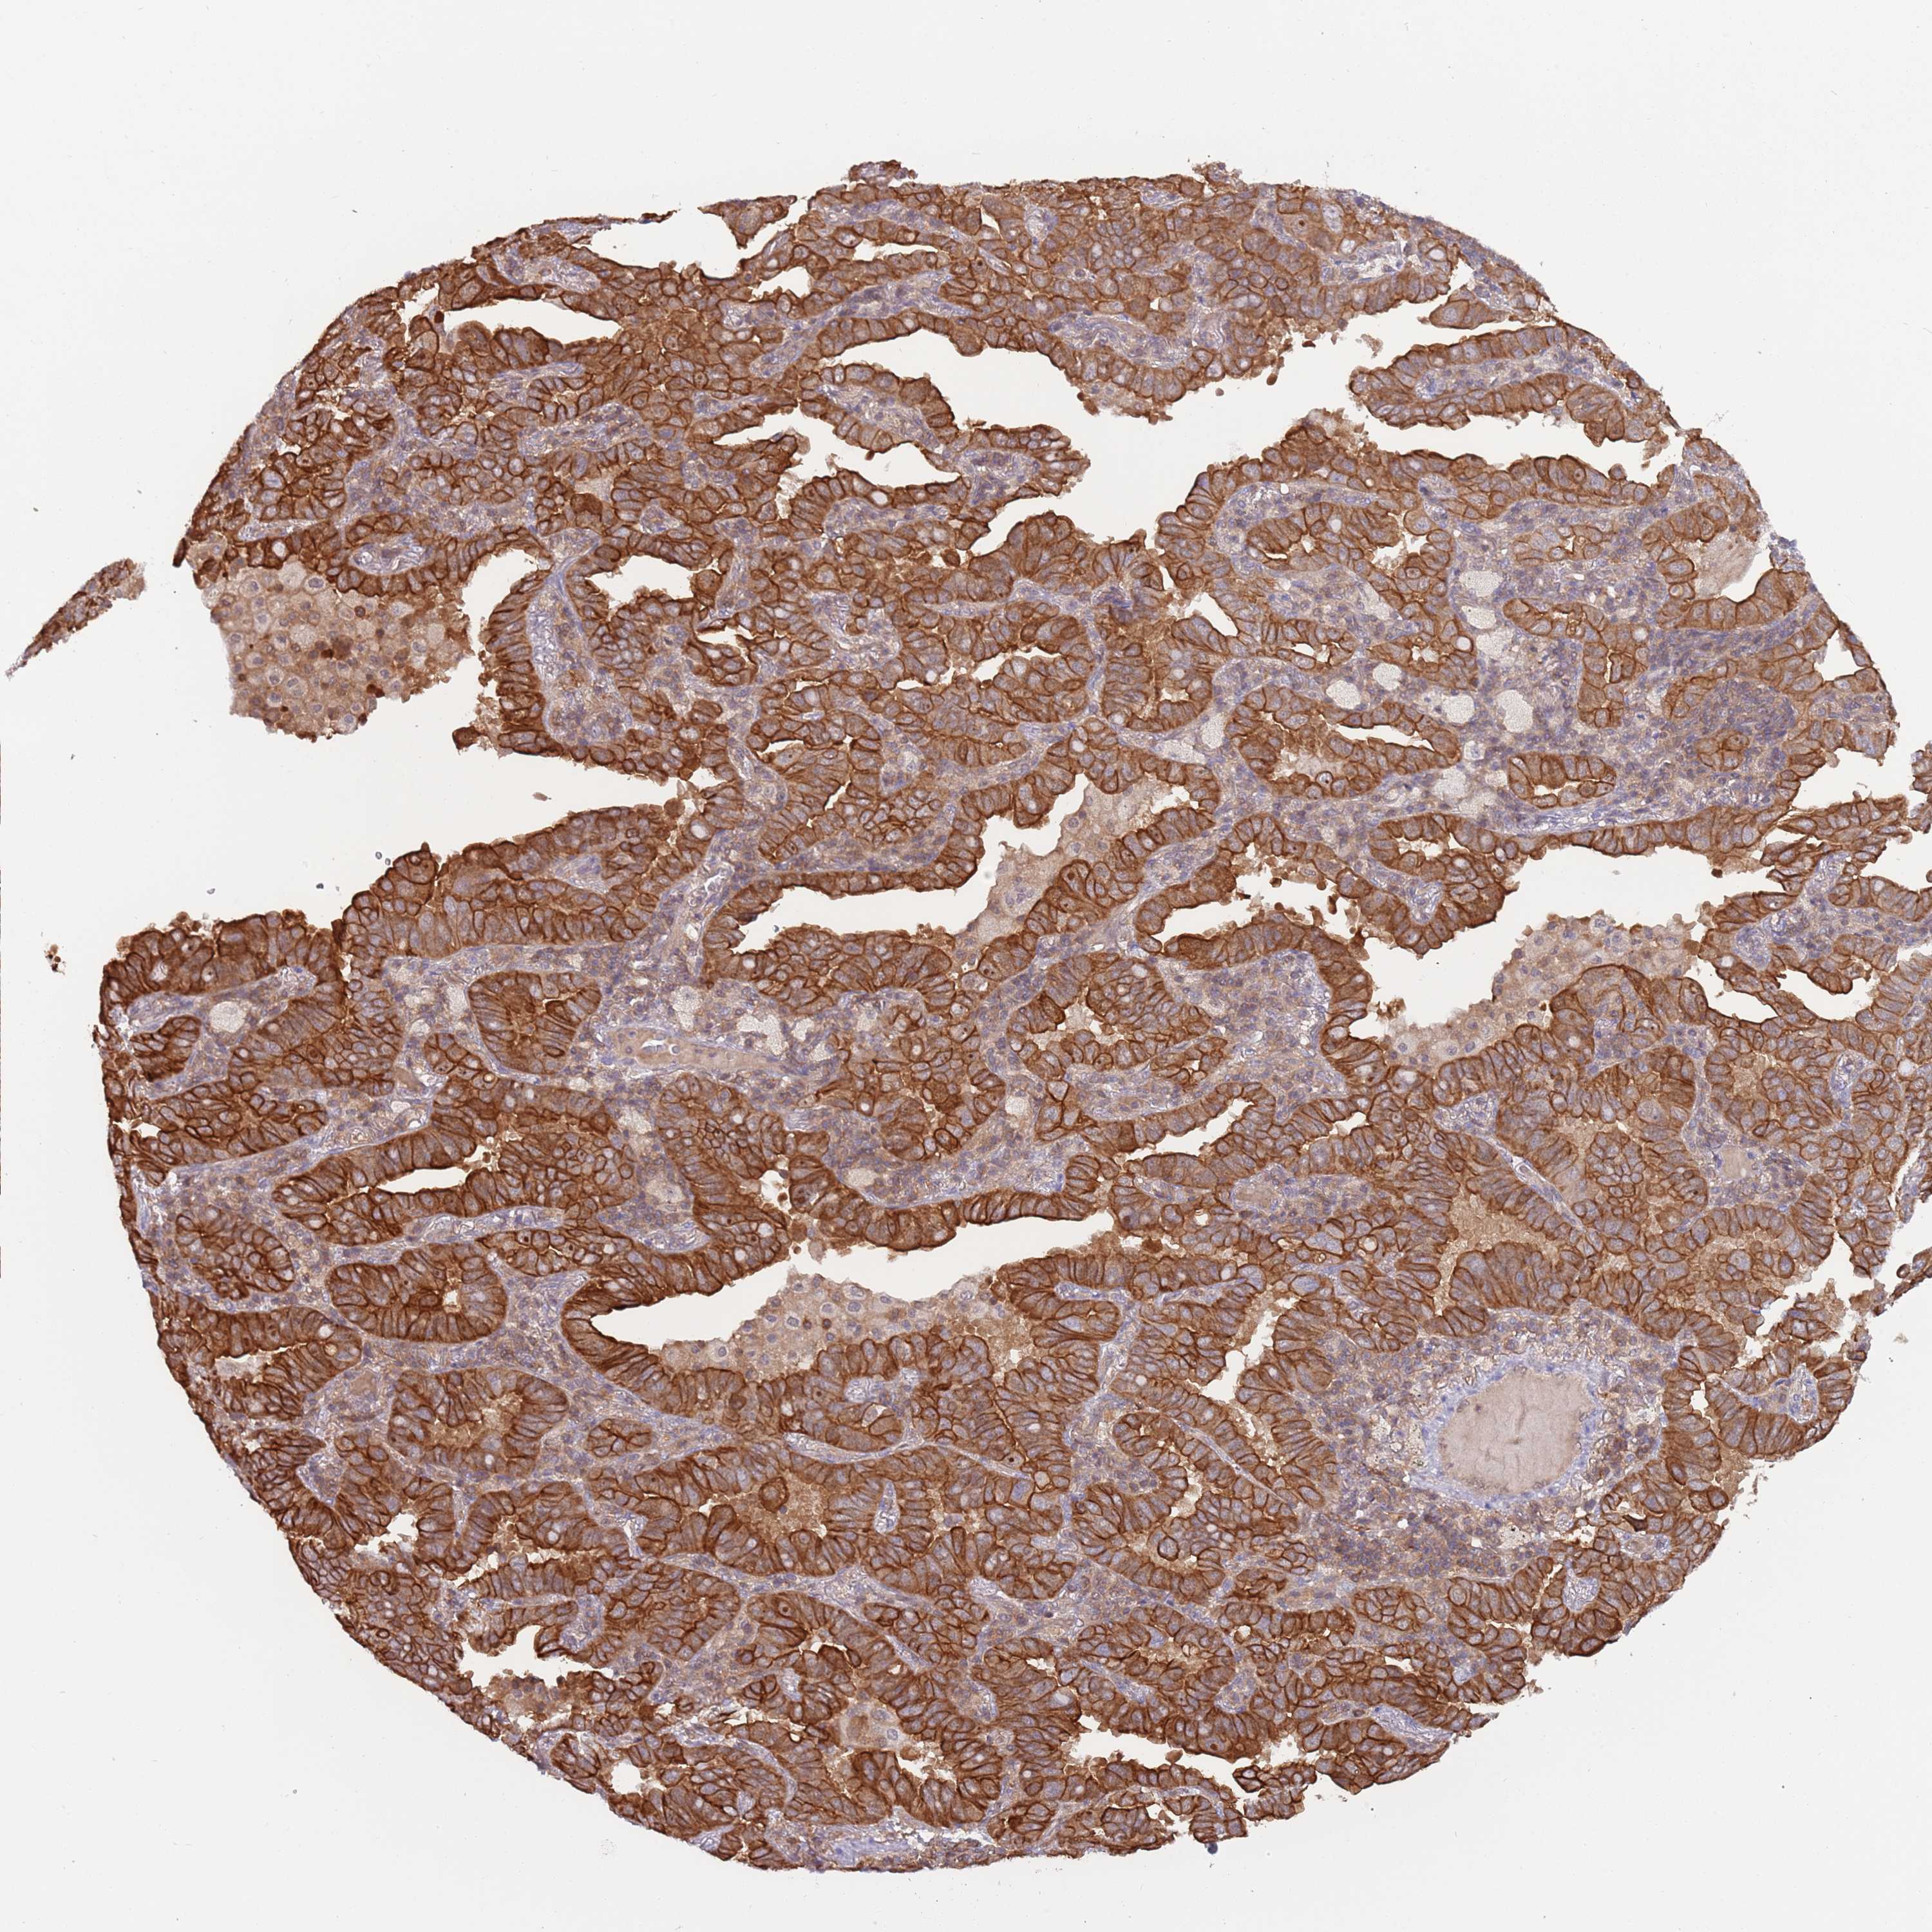

CANCER LUNG CANCER Show tissue menu

LUAD TCGA LUAD VALIDATION LUSC TCGA LUSC VALIDATION PROTEIN LUAD CPTAC PROTEIN LUSC CPTAC PROTEIN EXPRESSION